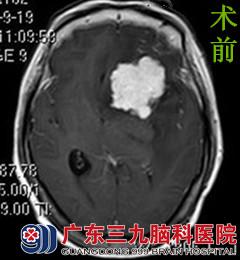

于是,曾阿姨一家人来到广东三九脑科医院,行头颅MR检查提示左侧额部示一团块状异常信号影,病变宽基底与前颅底相连,大小约4.87cmX3.87cmX2.70cm,邻近脑组织受压推移。左侧侧脑室受压明显变窄,中线结构向右偏移。完善相关检查后,由综合神经外科的鲁明主任主刀,在全麻下行左侧蝶骨嵴脑膜瘤切除术,术中显微镜下见灰白色肿瘤组织位于左侧鞍旁蝶骨嵴区,分块全切肿瘤,术中视神经、动眼神经、颈内动脉及其分支血管保护完好,手术顺利结束,术后患者未出现任何手术并发症,经系统治疗后康复出院。术后病理结果为:过渡型脑膜瘤(WHO I级)。